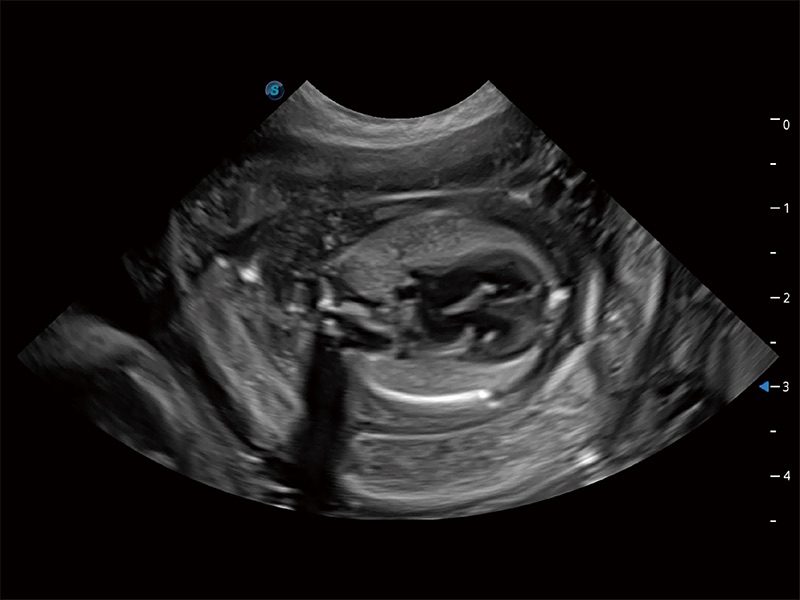

(犬)胎儿四腔心

优异的基础图像

ProPet 80 全新的动物超声智能软件和丰富的探头群,为动物医生提供了高清晰度和精细分辨率的图像,无论在宠物、马科、畜牧还是实验室动物等应用中都可以轻松应对,为您的日常工作带来满意的体验。